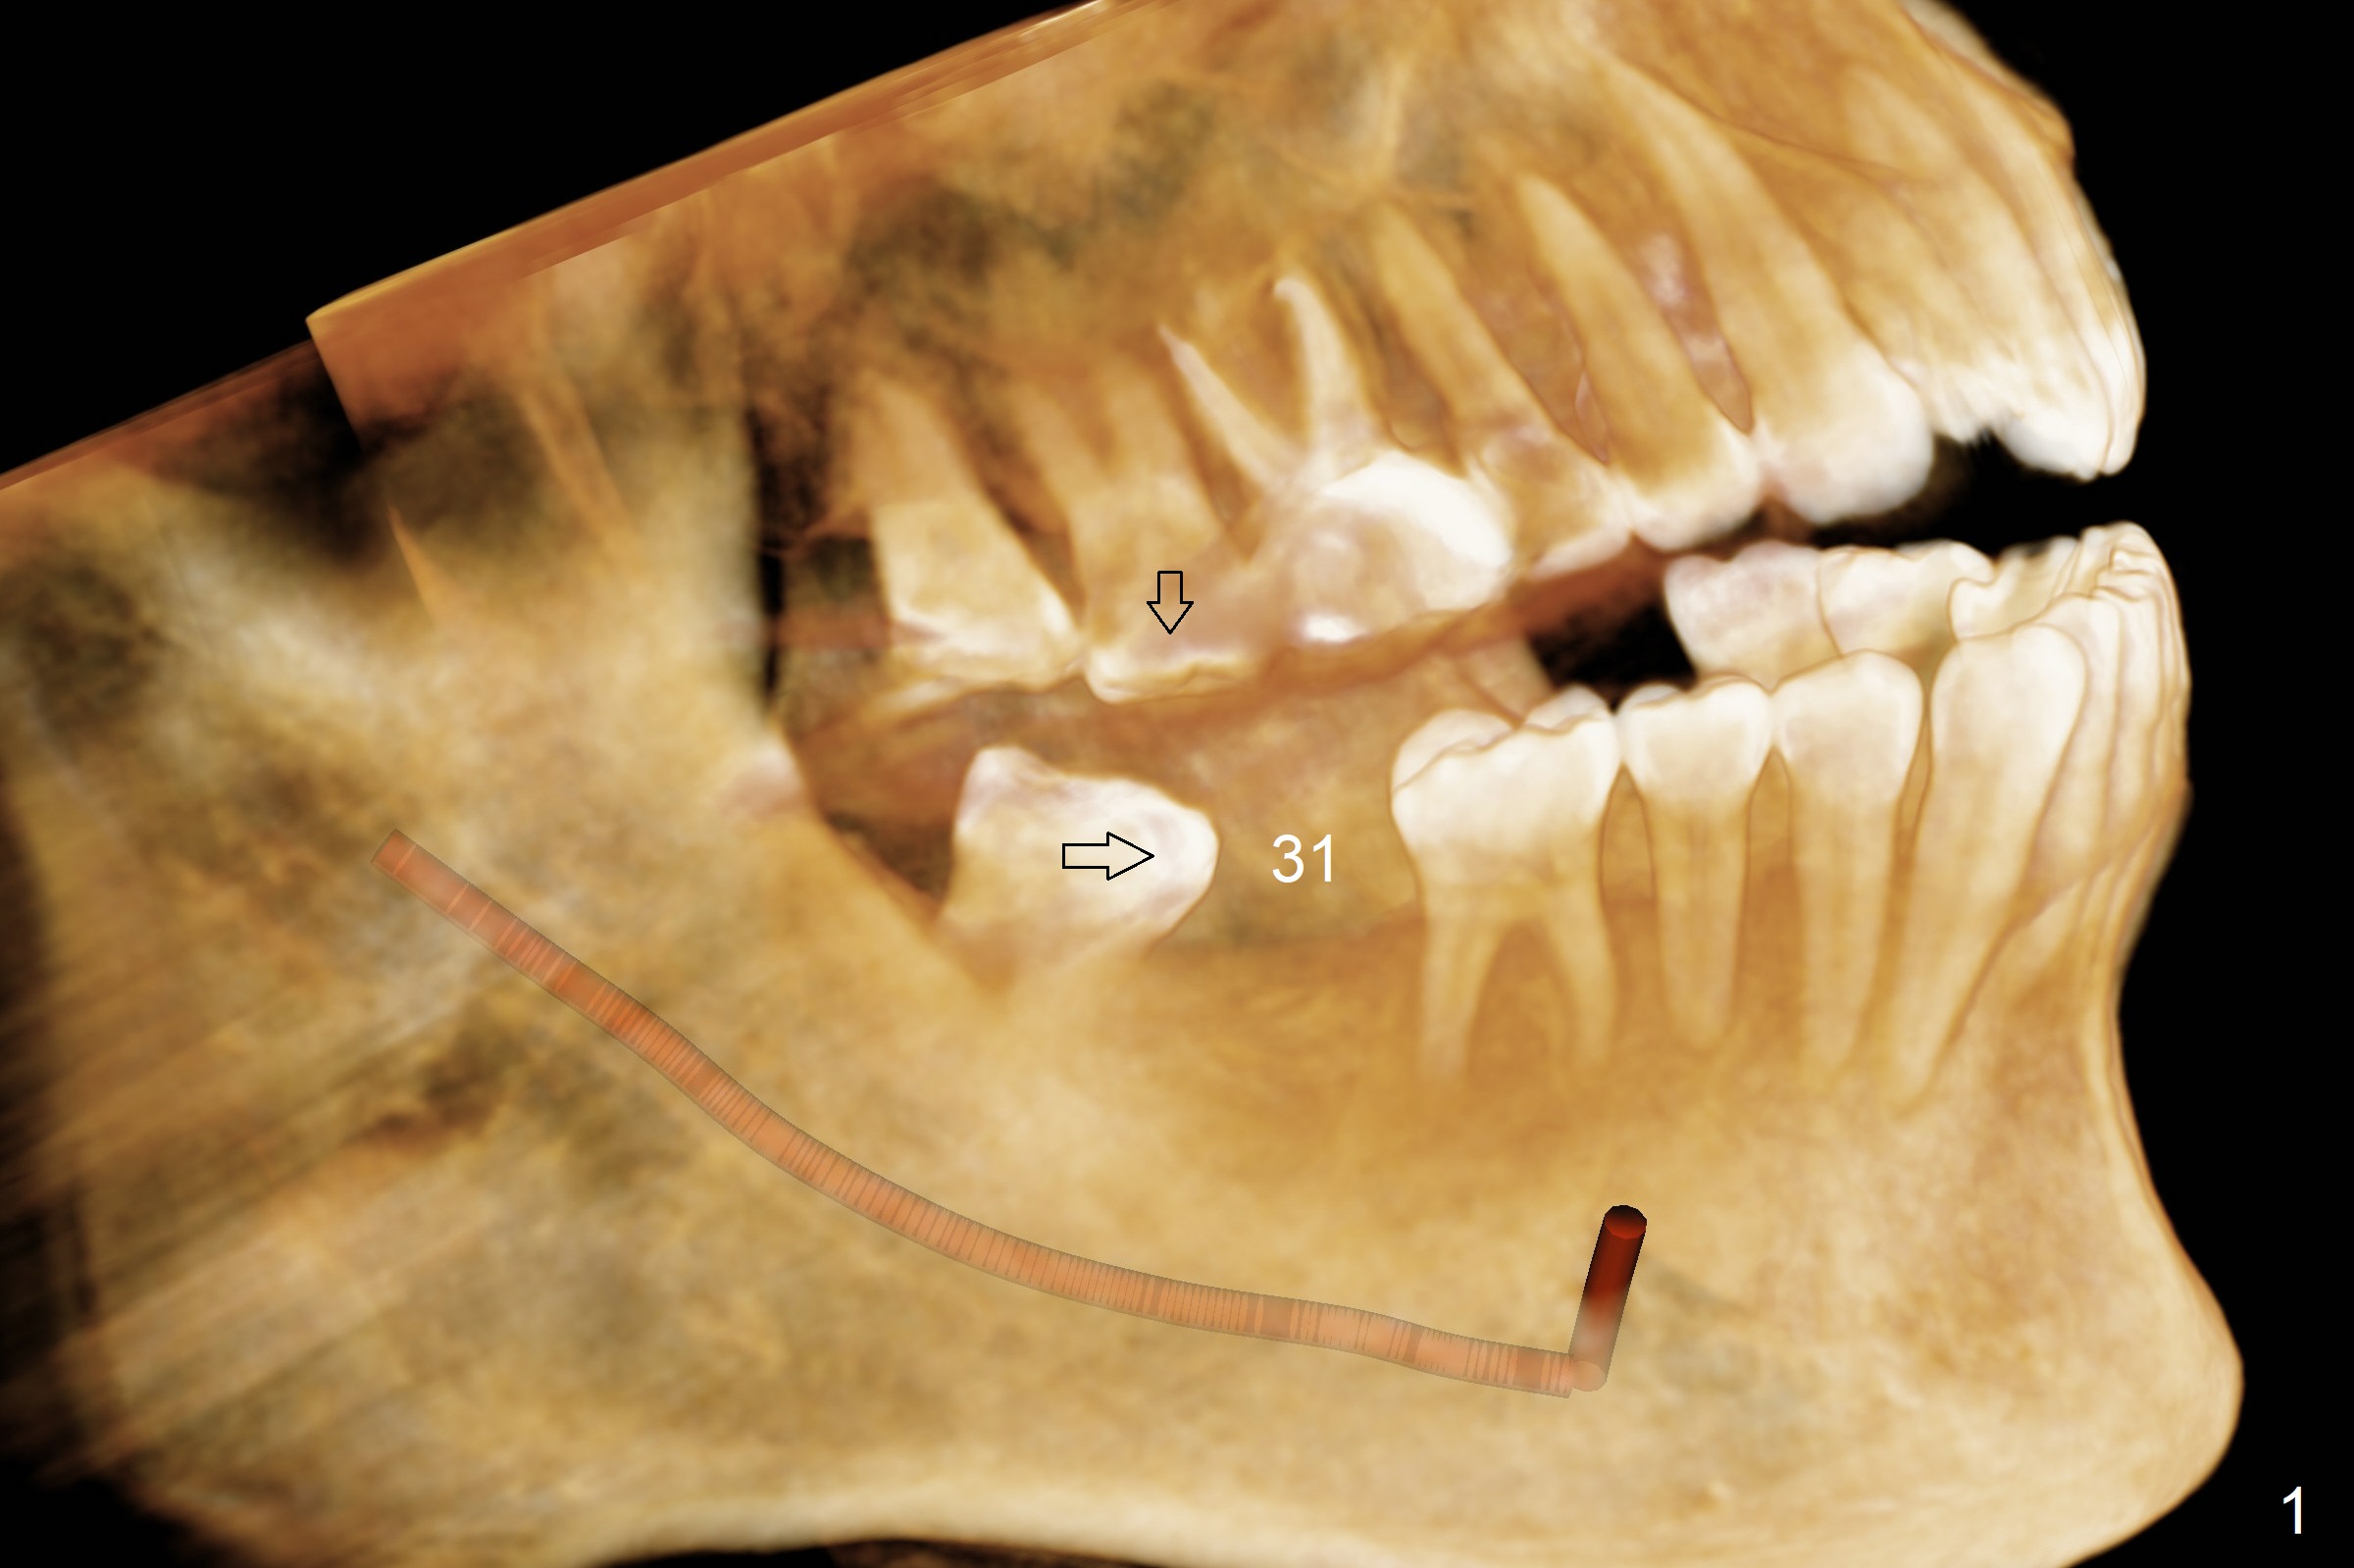

A 58-year-old man has lost the teeth #18 and 31 with supraeruption of the opposing teeth and mesial tilt of the distal tooth (Fig.1,2 arrows). Since the supraeruption is less severe on the right side (due to the presence of the tooth #32 as an antagonist to supraeruption of the tooth #2 (Fig.1' (arrow), as compared to Fig.2')), an implant will be placed at #31 with guide first (Fig.3 (coronal section of CT)). It is pity not to ask the lab to place the implant slightly distal for #32 upright. It is important to take impression for precise analysis of localized malocclusion. Intrusion of #2,15 will be initiated at the same time (Fig.4,5 (axial sections)), while the implant placement at #18 will be done last (Fig.6).